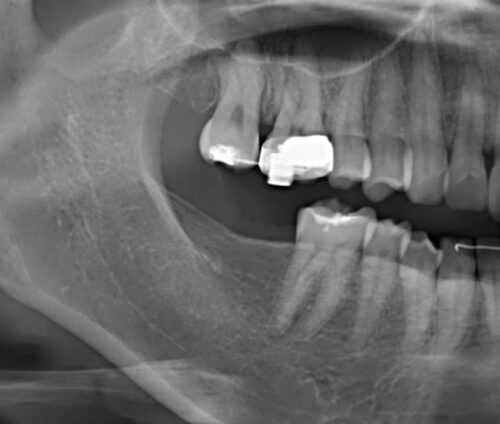

30代女性。矯正歯科にて全額矯正を行った際、下顎7番の長期欠損による上顎7番の挺出も改善。最終的に欠損部をどうするかという話になり、矯正医からインプラント治療を勧められ当院に来院された患者さんです。

下顎7番にインプラントを埋入。